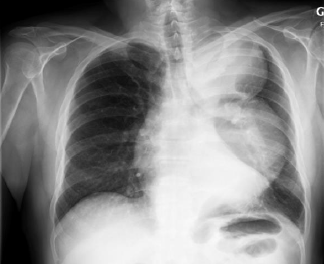

Pathologies médiastinales